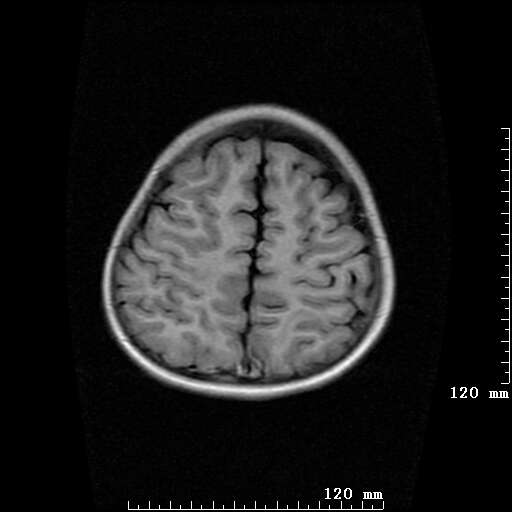

女,7岁,三岁才说话、走路。现智力尚可,走路不稳。临床怀疑大脑发育不全。

考虑 脑白质发育不良

脑折质变薄,双侧侧脑室稍扩张,支持考虑脑折质发育不良

侧脑室周围白质软化症。

考虑胼胝体发育不全,髓鞘形成不良。

支持考虑胼胝体发育不全,髓鞘形成不良。

脑裂畸形伴灰质异位

侧脑室周围白质数量减少,侧脑室不对称性扩大,左侧侧脑室后角呈方形改变,脑沟加深,结合临床考虑脑室周围白质软化症(pvl)。期待结果!

只看出灰质异位

支持脑白质发育不良。